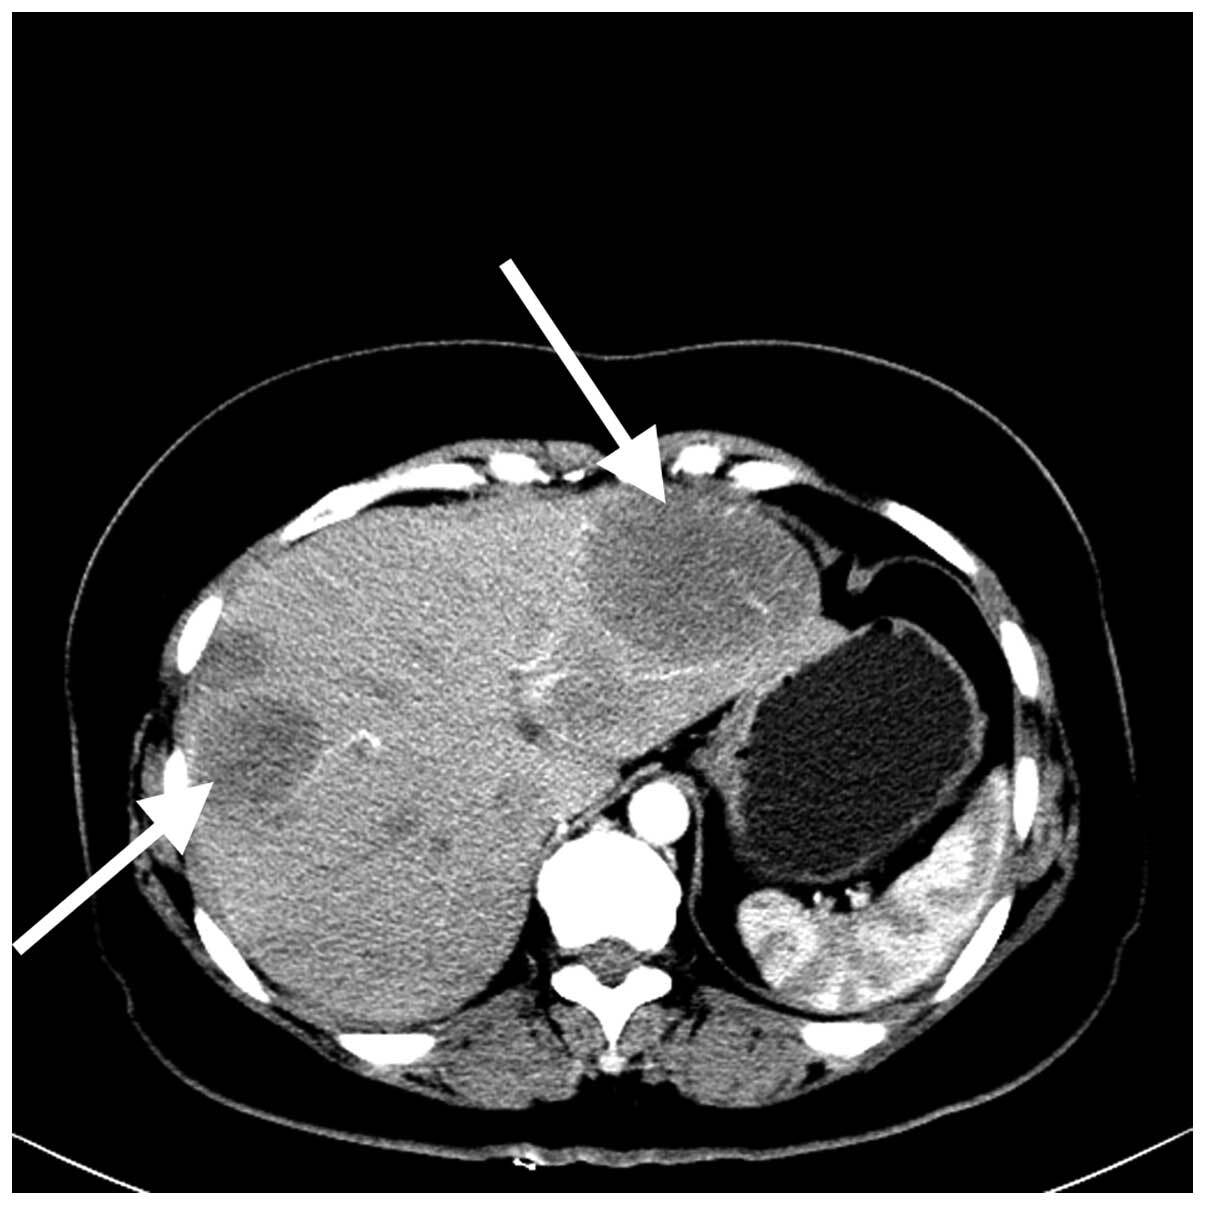

Метастазы в печени. Возможные варианты лечения | Пикабу